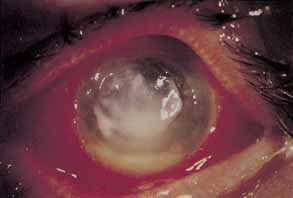

Infectious keratitis is the single most feared complication of contact lens wear.138 Corneal infections may range from small peripheral ulcers to large suppurative central ulcers. Infectious ulcers must be differentiated from sterile ulcers, particularly in association with disposable extended lens wear. Bacterial keratitis occurs most frequently in association with extended soft contact lens wear and least frequently among rigid PMMA wearers. Bacterial keratitis is by far the most frequent form of infectious keratitis associated with contact lens wear, with Pseudomonas aeruginosa being the most frequent isolate (Fig. 5). In most cases of infectious keratitis, there is an identifiable breach of contact lens care protocol that predisposes the patient to infection. It is imperative to make a swift and accurate diagnosis of infectious keratitis and to initiate appropriate topical antibiotic therapy to minimize visual loss secondary to stromal scarring.

Fig. 5 Central Pseudomonas keratitis with hypopyon.